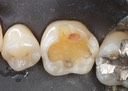

Joe Cha #3 pre-op